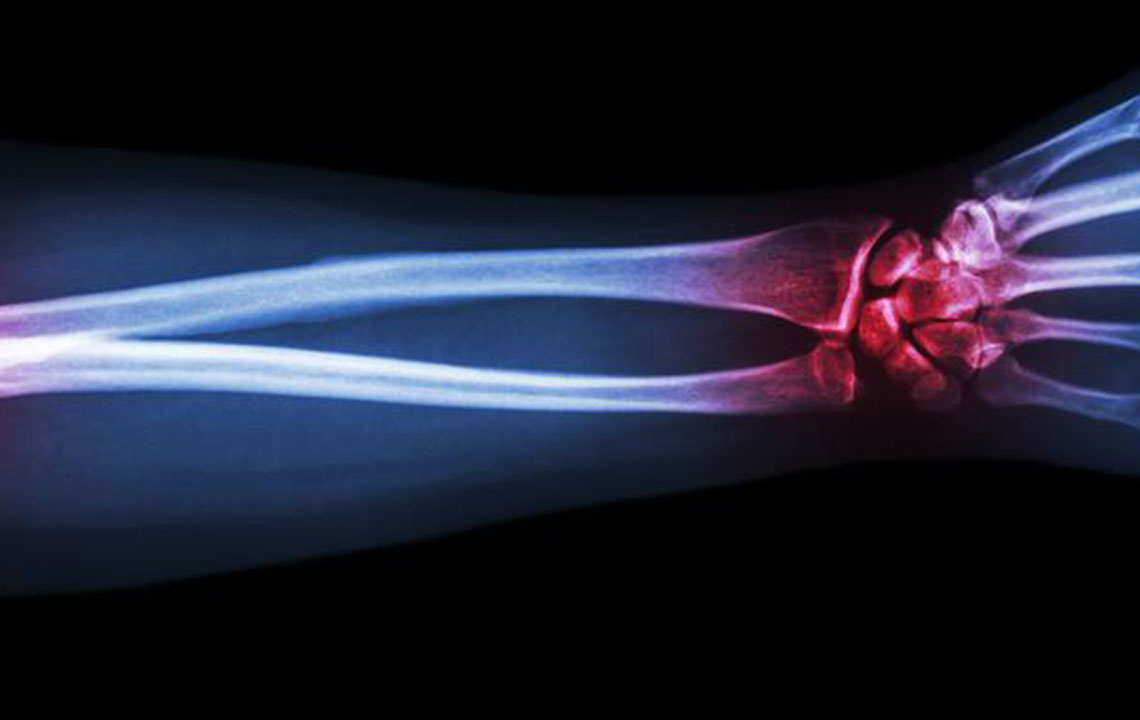

Gout is a type of arthritis that primarily attacks the joints and other body parts like the ears, wrists, knuckles, knee, ankles, and other small joints. It is often characterized by painful swelling, stiffness, and inflammation of these affected joints. The swelling and stiffness are mainly the results of excess levels of uric acid forming crystals in the joints. The pain is due to the inflammatory response to the crystals formed.

The deposition of uric acid crystals in the joint causes inflammation and makes the movement of the joint agonizing. The elevated levels of uric acid in the system also causes the depositing of crystals in the kidney, which, in turn, leads to stone formation.

The most common sign of a gout attack is the night-time swelling of the big toe followed by redness, tenderness, redness, and gut-wrenching pain. This attack might continue for days or even weeks before the pain goes away completely. Swelling causes pain and pain induces swelling. Hence, it is important to address both.